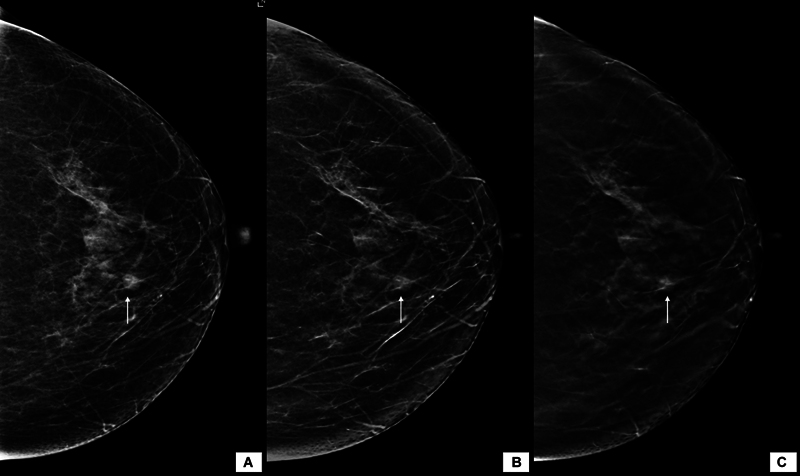

合成乳房x线摄影(SM)是指从数字乳房断层合成(DBT)数据中获得的二维(2D)图像。与传统的全视野数字乳房x线摄影(FFDM)加断层合成相比,它可以减少辐射剂量和扫描时间。目的比较二维FFDM与DBT合成乳房x线照片在诊断人群中的诊断效果。材料与方法经研究所伦理委员会批准,在2年内共获得1468张含FFDM和SM + DBT的乳房x线照片并进行分析。根据2013年美国放射学会乳腺成像报告和数据系统(BI-RADS)词汇,对图像进行报告和比较,包括乳房密度、肿块形态学特征、钙化、不对称或结构扭曲的存在,然后进行BI-RADS分类。采用Kappa值研究两种模式之间的一致性,并记录两组的辐射暴露剂量。结果FFDM和SM + DBT在乳腺密度、肿块特征和钙化检测方面具有很强的一致性(kappa >.8)。SM + DBT对乳腺密度和肿块密度的分期下降无统计学差异。SM组乳头乳晕复合体的可视化较差(50.34% vs. 76.29%),且存在SM特异性伪影,主要与重建算法有关。SM的辐射剂量较高。结论FFDM与SM + DBT诊断效果相当。后者可能对乳房致密的患者特别有用。

Background  Synthesized mammography (SM) refers to two-dimensional (2D) images derived from the digital breast tomosynthesis (DBT) data. It can reduce the radiation dose and scan duration when compared with conventional full-field digital mammography (FFDM) plus tomosynthesis. Purpose  To compare the diagnostic performance of 2D FFDM with synthetic mammograms obtained from DBT in a diagnostic population. Materials and Methods  A total of 1,468 mammograms with both FFDM and SM + DBT images were obtained and analyzed over 2 years, after obtaining approval from the institute ethics committee. The images were reported and compared as per the 2013 American College of Radiology Breast Imaging Reporting and Data System (BI-RADS) lexicon in terms of breast density, morphological features of mass, calcifications, and presence of asymmetry or architectural distortion followed by the BI-RADS category. The agreement between the two modalities was studied using the Kappa value, and the radiation exposure dose was recorded in both groups. Results  FFDM and SM + DBT showed strong agreement for breast density, mass characteristics, and detection of calcifications (kappa > 0.8). Downstaging of breast density and mass density were seen by SM + DBT without any statistically significant difference. The nipple-areola complex visualization was poor in SM (50.34 vs. 76.29% in FFDM), and there were SM-specific artifacts mainly related to the reconstruction algorithm. The radiation dose was higher with SM. Conclusion  FFDM has comparable performance to SM + DBT in diagnostic setup. The latter may be particularly helpful in patients with dense breasts.